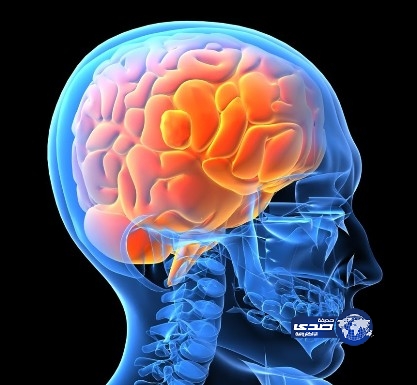

دماغ

السلمان: أكثرُ المشاعر تدميرًا لخلايا الدماغ الحزن والقلق الشديد

اكتشفي الفرق بين أدمغة الرجال والنساء

دماغ الإنسان مبرمج للتفاعل مع “الأحبة”